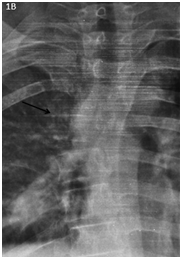

During a soccer game, the patient suffered a trauma to the thoracolumbar region. It started with pain in the same area, and outpatient treatment was based on NSAIDs with partial improvement. Two days after the incident the patient started with cough of nocturnal predominance, insidious onset, in long accesses, without expectoration, and without apparent trigger. His is evaluated in the ER triage area with clinical examination and X-ray. The relevant data in physical examination includes: thoracic scoliosis with deviation to the right, decreased amplexation, decreased respiratory sounds in right hemithorax region. The patient had pain on palpation in spinous processes T4, T5, T6. The chest x-ray revealed the absence of 5, 6 and 7 right costal arcs with dorsal dextroescoliosis (Figures 1A and 1B). No fever or other clinical data was given, and the patient was discharged with alarming symptoms and Ibuprofen.

<strong>Figure 1A </strong> Chest X-ray with absence of 5,6 and 7 right costal arcs with dorsal dextroescoliosis.

Figure 1A Chest X-ray with absence of 5,6 and 7 right costal arcs with dorsal dextroescoliosis.

<strong>Figure 1B </strong> T4 listhesis (black arrow).

Figure 1B T4 listhesis (black arrow).